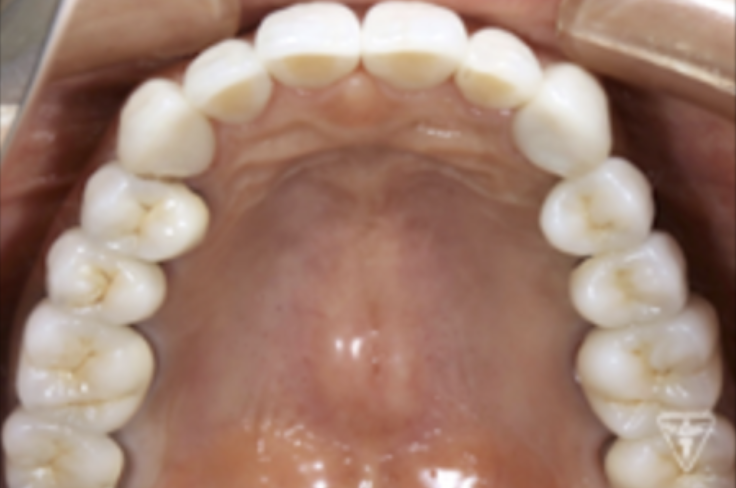

咬合平面の評価(SHILLAⅡの平面板による)

治療後